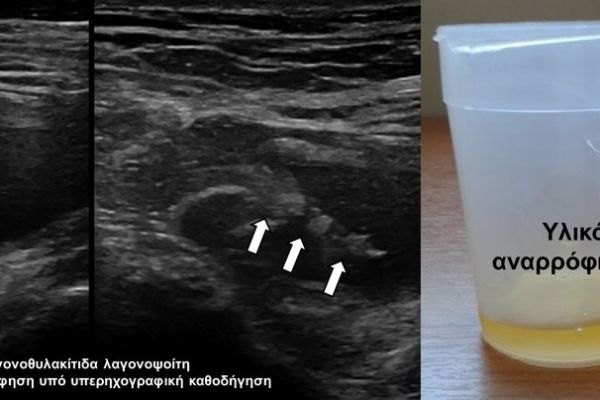

Η οστική βιοψία και η βιοψία όγκων μαλακών μορίων χρησιμοποιείται για την ιστολογική διάγνωση αλλοιώσεων (καλοήθων - κακοήθων / πρωτοπαθών ή μεταστατικών) ή για τη λήψη υλικού προς καλλιέργεια ώστε να αναδειχθεί το μικρόβιο που προκαλεί τη λοίμωξη του μυοσκελετικού συστηματος (πχ σπονδυλοδισκίτιδα). Η βιοψία υπό συνεχή απεικονιστική καθοδήγηση συμβάλλει στην υψηλή ακρίβεια τοποθέτησης της βελόνης εντός της βλάβης με ασφαλή προσπέλαση. Η χρήση σύγχρονων ομοαξονικών συστημάτων βιοψίας (coaxialtechnique) επιτρέπει την λήψη πολλαπλών δειγμάτων με μια μόνο παρακέντηση.